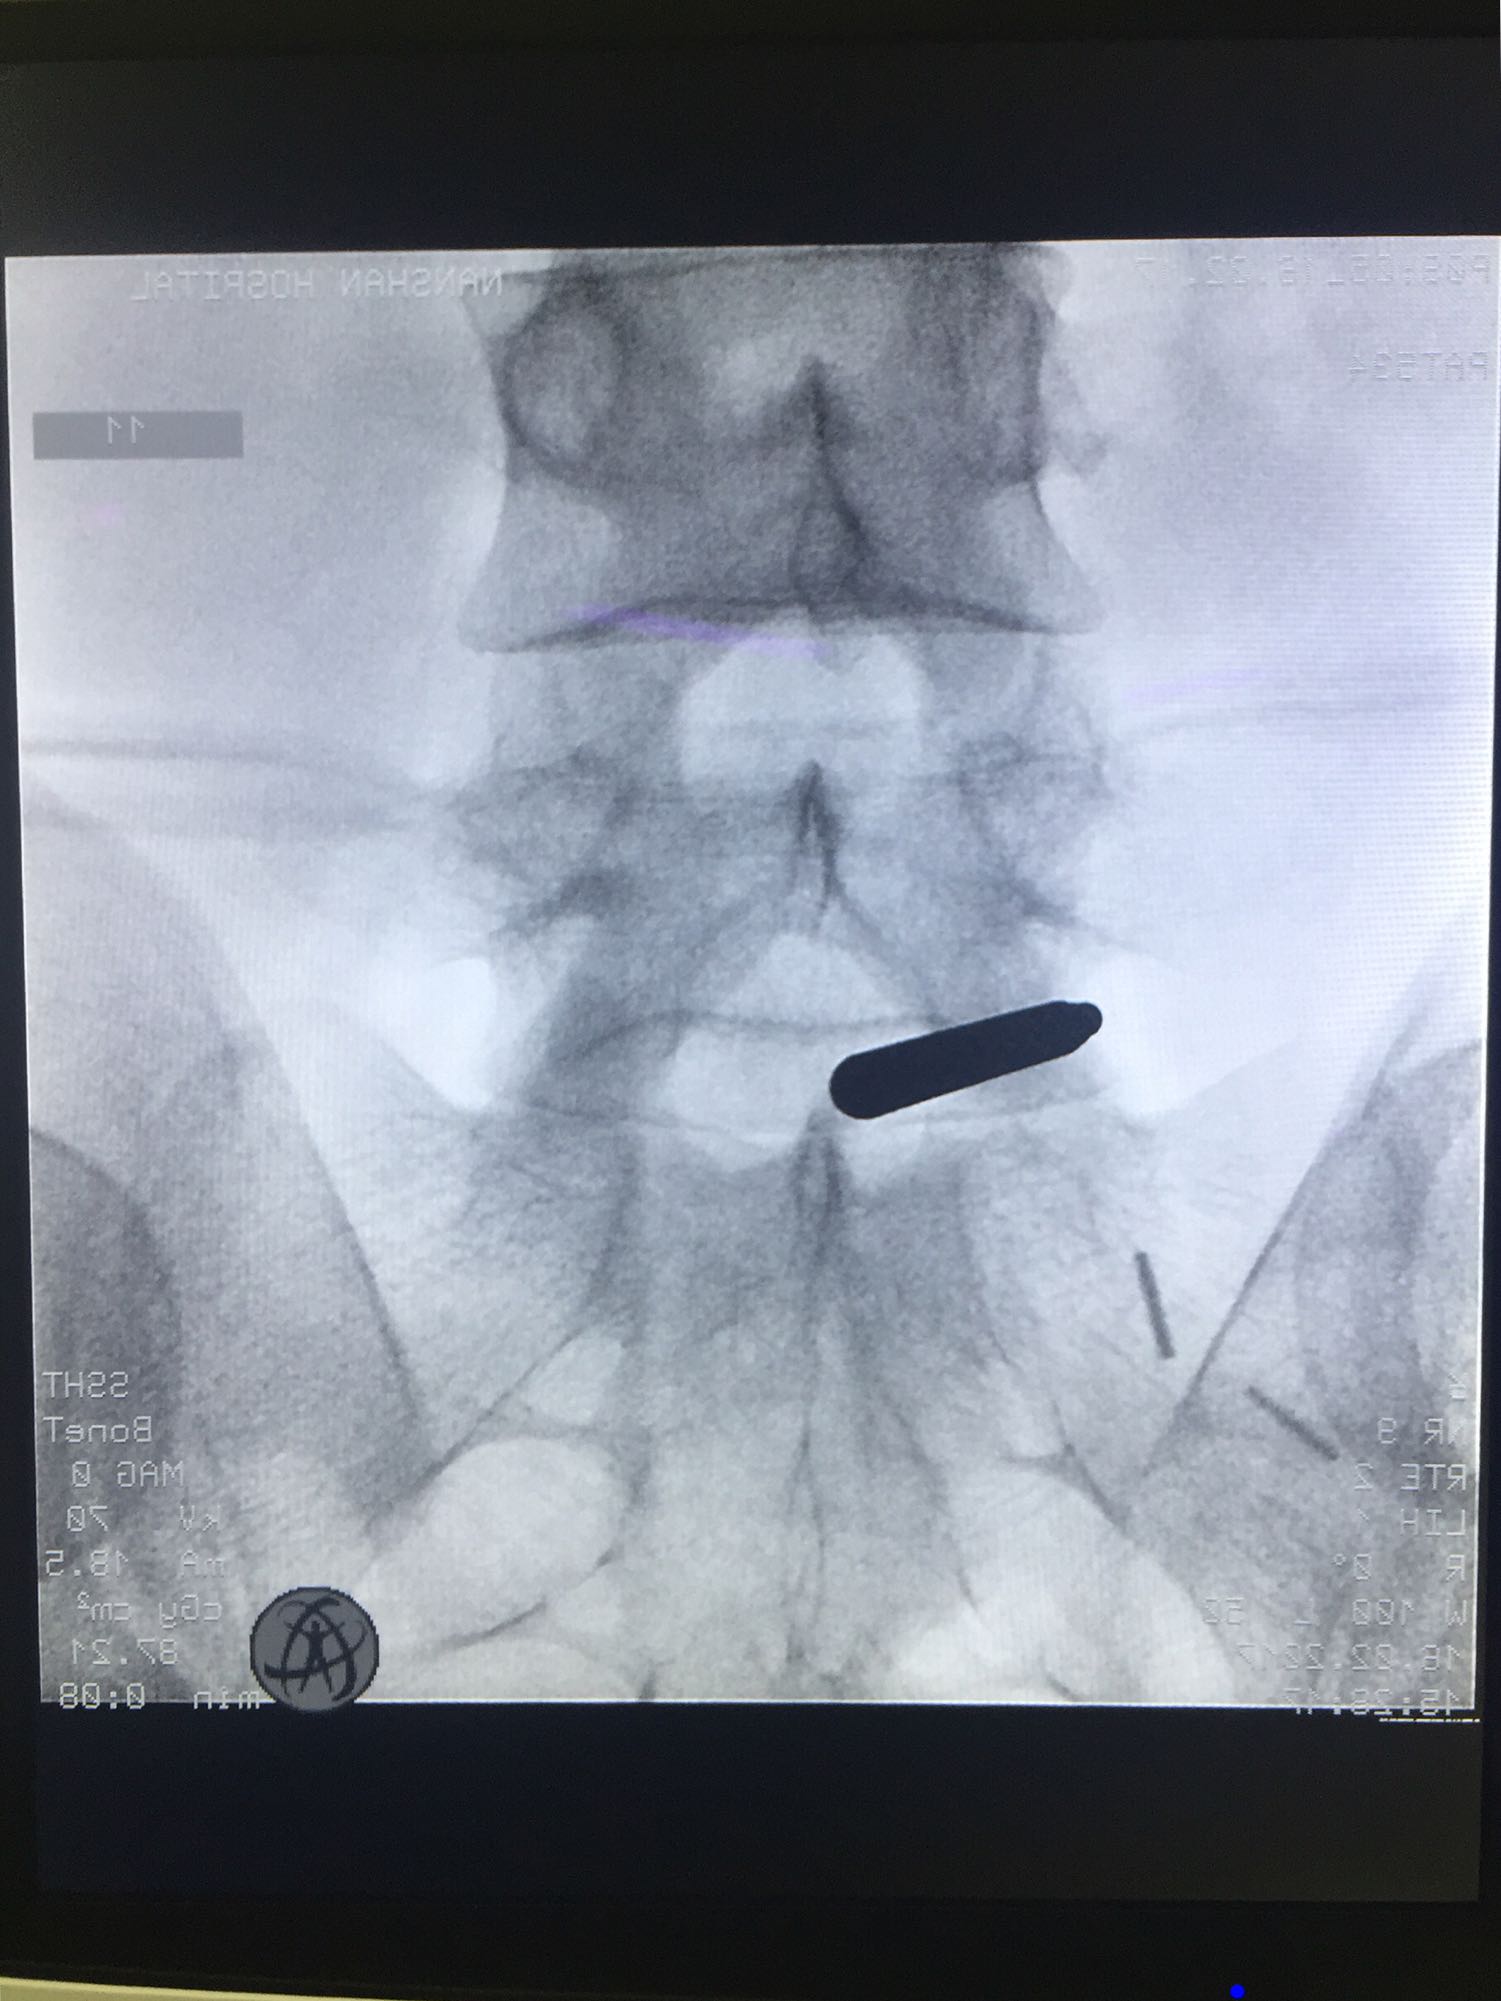

椎间孔镜下腰5骶1椎板间隙入路髓核摘除术

诊断:腰5骶1椎间盘突出症 治疗方案:椎间孔镜下经椎板间入路髓核摘除术